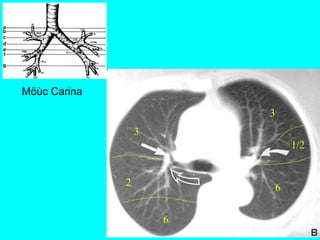

CAÂY PHEÁ QUAÛN VAØ PHAÂN

THUØY PHOÅI

+CT cho chi tieát giaûi phaãu toát raát nhieàu so

vôùi X quang qui öôùc

+Phaân tích hình aûnh CT

-Caây pheá quaûn

-Phaân thuøy phoåi

-Raõnh maøng phoåi

Ngang möùc

cung ñoäng

maïch chuû

3

2

1/21

6

Möùc Carina

1/2